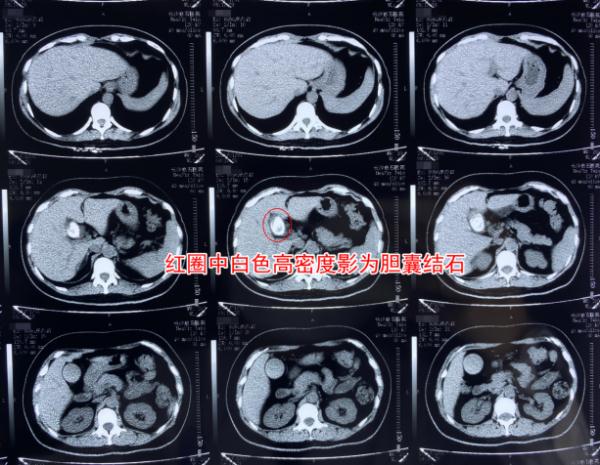

王女士术前CT检查结果局部图

王女士被确诊患有胆囊结石并胆囊炎,不仅结石最长径达3.2公分,且胆囊中有大量的胆汁淤积,已达到了手术治疗指征。据长沙京石医院肝胆外科主任李小攀介绍:“患者的胆囊结石非常大,并且正好嵌顿在胆囊颈部,如果不及时手术取出的话,会导致胆囊逐渐失去功能,也就失去了保胆取石的机会。并且一旦并发严重感染,还可能出现胆囊化脓穿孔等危险情况。”